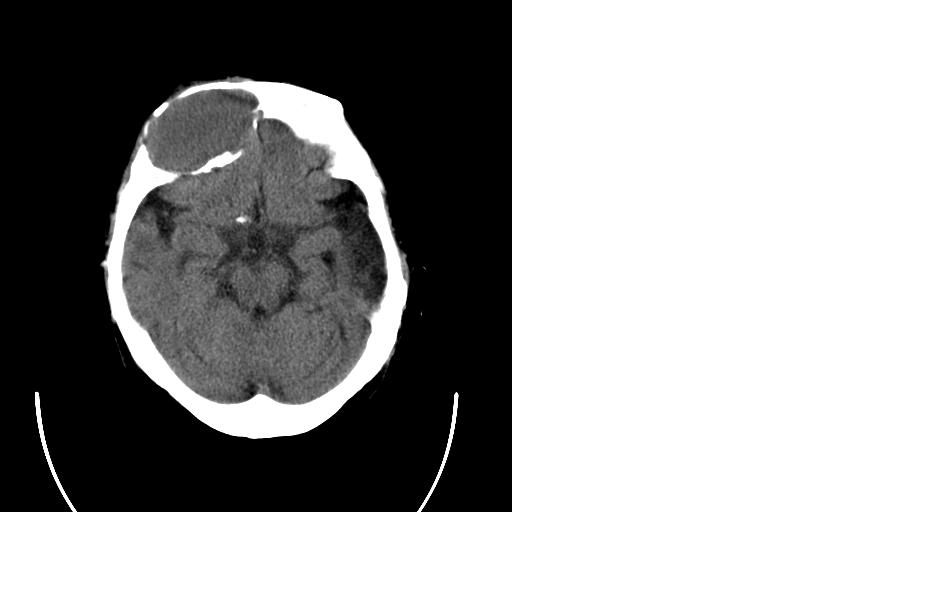

女,77岁,渐进性突眼2年,无其他明显症状

病变位于起源于右侧筛窦,右侧眼球受压移位,右侧大脑半球额叶白质受压塌陷,水肿不明显.额骨呈压迫性骨质吸收变薄.考虑脑膜瘤,建议增强吧

右额窦粘液囊肿,向前累及筛窦并进入眼眶使眼球前突;向下进入颅内右额叶脑质及侧脑室受压

病变应起源于右侧额窦/或额骨板障,肿块周围骨包壳尚完整,呈膨胀挤压改变,右侧眼球受压移位,右侧大脑半球额叶白质受压塌陷,水肿不明显.考虑为良性病变,骨纤维瘤/或骨嗜酸性肉芽肿? 建议增强吧

支持:病变的起源我乐意定在右额窦。右额窦粘液囊肿或粘液腺癌累及筛窦、眼眶使眼球前突;向下进入颅内右额叶脑质及侧脑室受压变形。

右侧筛窦类圆形实质性肿块向颅内呈膨胀性生长,边缘较为光滑,其内似见囊性低密度影,边缘骨壁受压变薄移位,部分骨质缺损破坏

定位:来源右额窦。定性:良性占位—额窦黏液囊肿。理由1、病灶中心位于右额窦区,侵及筛窦并向下向前压迫眼球2、骨质呈膨胀性改变,骨质弓形变薄但骨壳完整,如为恶性骨质应为侵蚀性破坏3、黏液囊肿好发于筛窦、额窦。